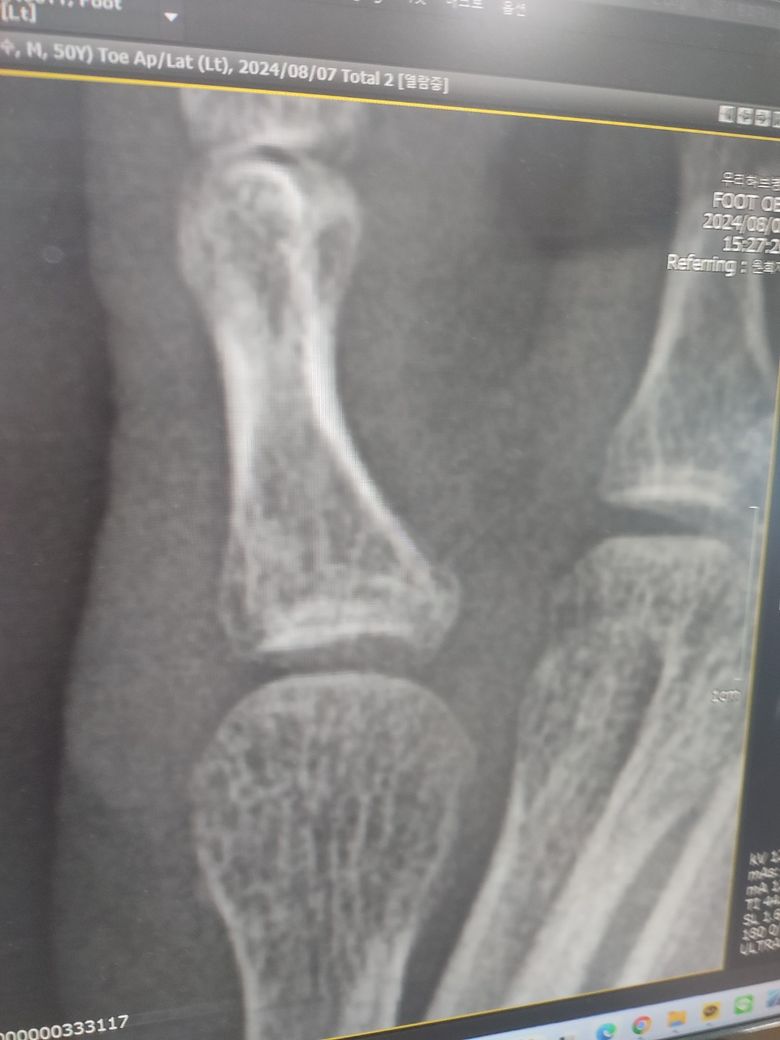

새끼발가락 골절 4개월차입니다.????

4개월전에 골절엑스레이판단 미스로 그냥 생활하다가 통증이 심해져서

2달뒤 ct로 골절판정받고 지난주에 엑스레이로 뼈가 다 붙었다고하는데..

사진첨부합니다.

골절이 붙은거 맞은지요

• 1번 째 사진

처음 골절되었을때 X-ray를 함께 보여주셔야 잘 붙어가고있는지 판단할 수 있겠습니다.